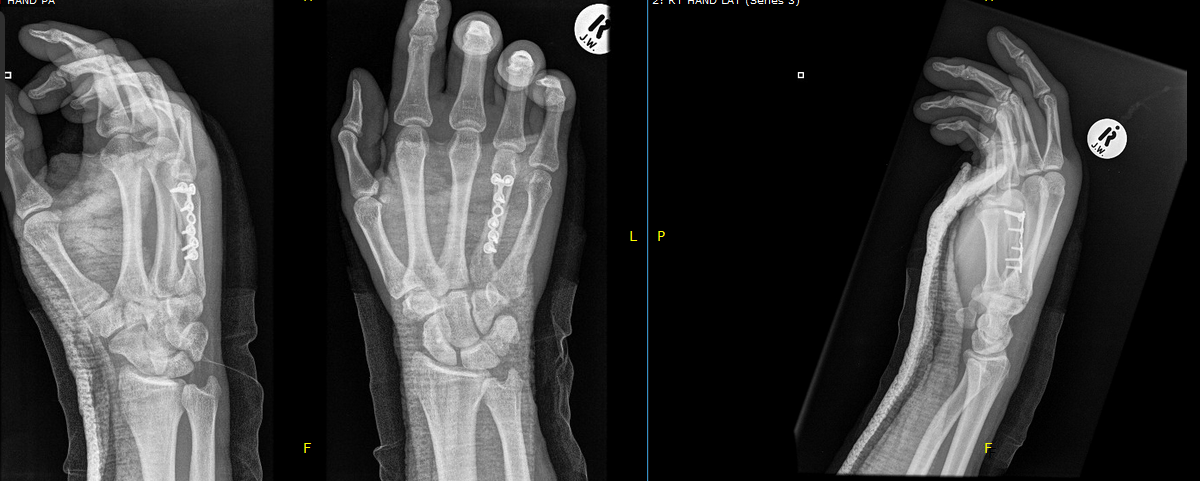

titanium finger